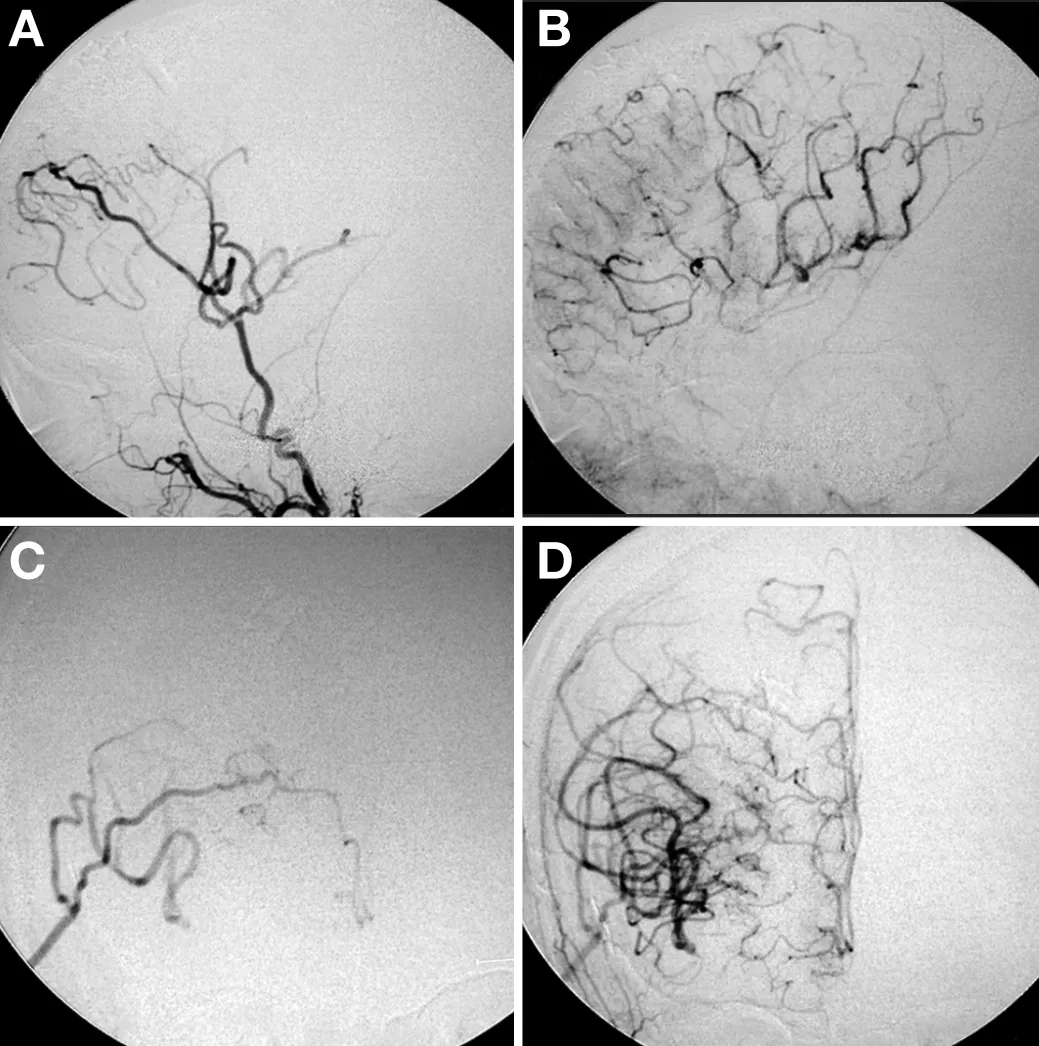

脑血管造影检查显示右侧颈内动脉末端存在严重狭窄,左侧A1段(大脑前动脉起始段)严重狭窄,左侧M1段(大脑中动脉起始段)轻度狭窄,并可见典型烟雾血管形成。影像学评估进一步发现双侧大脑前动脉区域血流灌注显著不足。

基于患者双侧大脑前动脉区域明显缺血的病情特点,治疗团队决定实施右侧颞浅动脉-大脑前动脉联合颞浅动脉-大脑中动脉双重直接搭桥术。该术式可同步改善大脑前动脉和大脑中动脉区域的血流灌注。

术后随访显示患者恢复顺利,未出现手术相关并发症。术后11天脑血管造影证实两处移植血管通畅良好,大脑前动脉区域血流灌注得到显著改善。该手术方案有效解决了传统单一搭桥术难以同时满足多区域血供需求的技术难题。